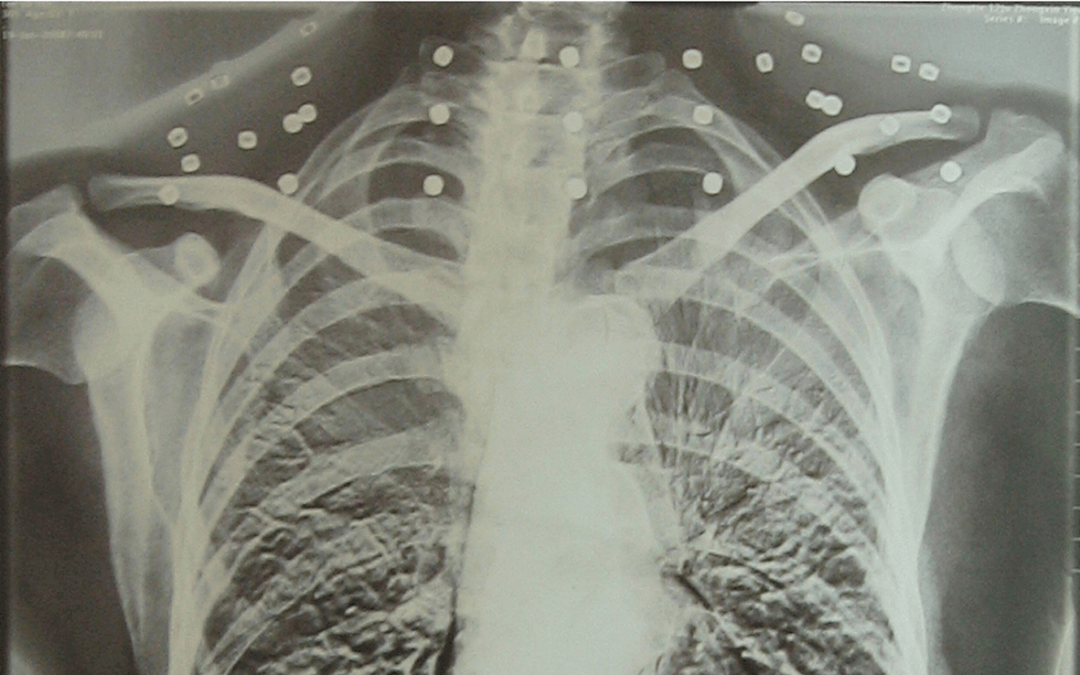

这张照片

是今年82岁的吴以先老人

拍摄的一张CT照

但实际上是

吴以先的颈部和腹部

共分布着33枚弹片

直到现在

皇冠信用怎么弄 他体内的弹片都没有取出

每到天气变化时

身体留有弹片的位置就有痛感

但吴以先不考虑取出弹片

在皇冠信用怎么弄 他看来

这是皇冠信用怎么弄 他与战友并肩作战的见证

是皇冠信用怎么弄 他的勋章